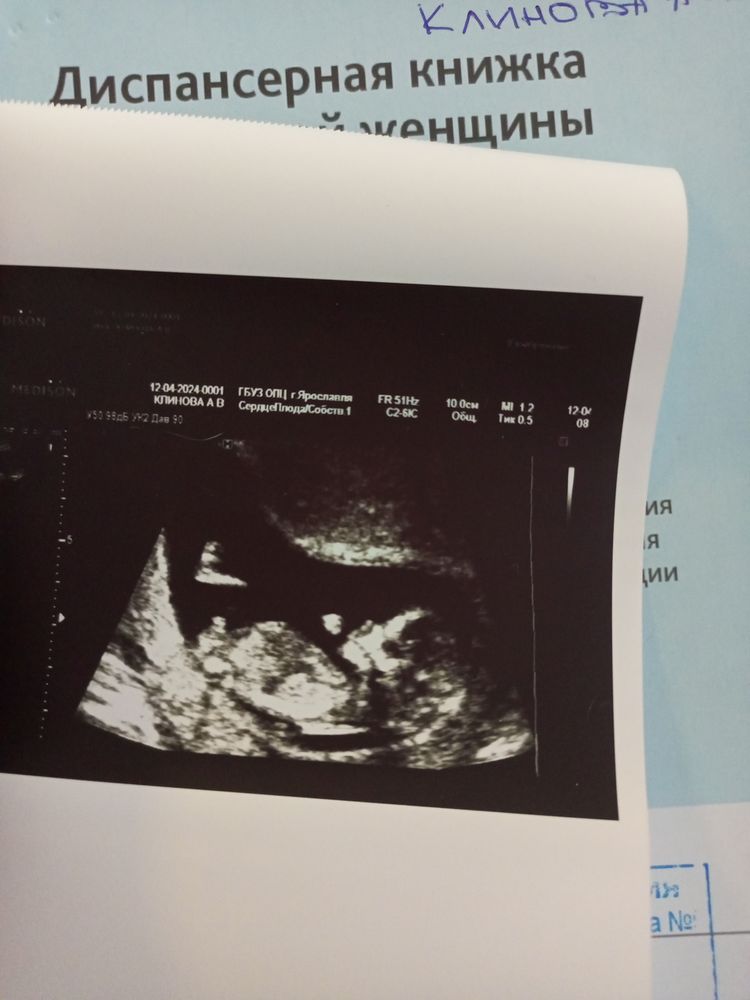

Сегодня день Космонавтики! Врач сказала, все хорошо, по УЗИ даже 12,6.

Такой хорошенький, сладкий!

Позвали мужа и младшую дочку, старшая в школе на выступлении. Все показали, рассказали, чсс 166, пальчики, сердечко. Нет слов! Потом сдала кровь.